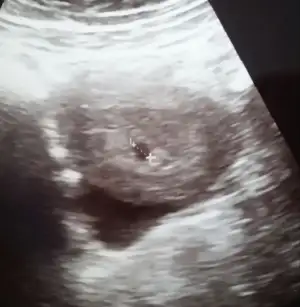

Bu da benim minigim teyzeleri